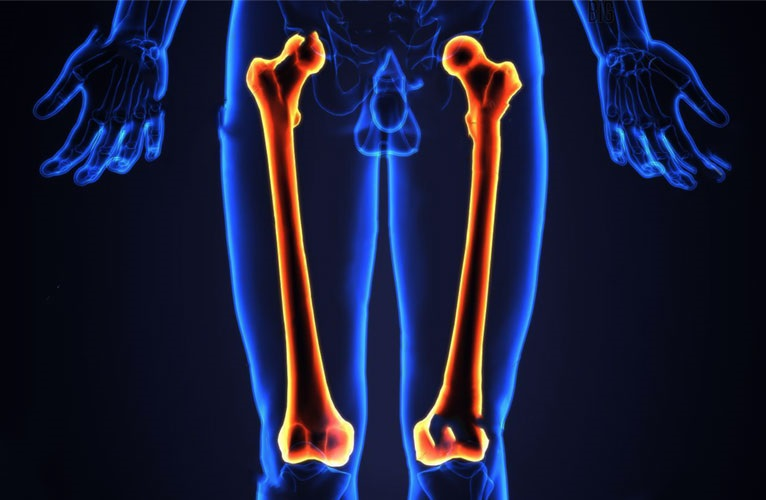

Xương đùi là xương dài nhất và chắc khỏe nhất trong cơ thể người, kéo dài từ hông đến đầu gối. Đây là xương chính của chân, có vai trò hỗ trợ trọng lượng cơ thể và có khả năng chịu được lực gấp 30 lần trọng lượng cơ thể. Việc hiểu rõ về giải phẫu xương đùi không chỉ giúp ích trong điều trị các chấn thương và bệnh lý liên quan đến chân, mà còn là nền tảng cho các nghiên cứu về tiến hóa và chức năng vận động của con người.

Xương đùi là xương lớn nhất và dài nhất trong cơ thể người, kéo dài từ hông đến đầu gối. Ở nam giới trưởng thành, xương đùi dài trung bình khoảng 48 cm và nặng khoảng 285 gr. Đây là một xương cứng, khỏe và không dễ gãy. Tuy nhiên, gãy xương đùi có thể gây chảy máu nghiêm trọng và là một tình trạng nguy hiểm, có thể đe dọa đến tính mạng.

Xương đùi là xương duy nhất ở đùi, có cấu trúc dày với các sụn ở hai đầu và một khoang chứa tủy xương. Là một loại xương dài, xương đùi có ba phần chính: Đầu gần, trục giữa và đầu xa. Cụ thể, cấu tạo xương đùi bao gồm: